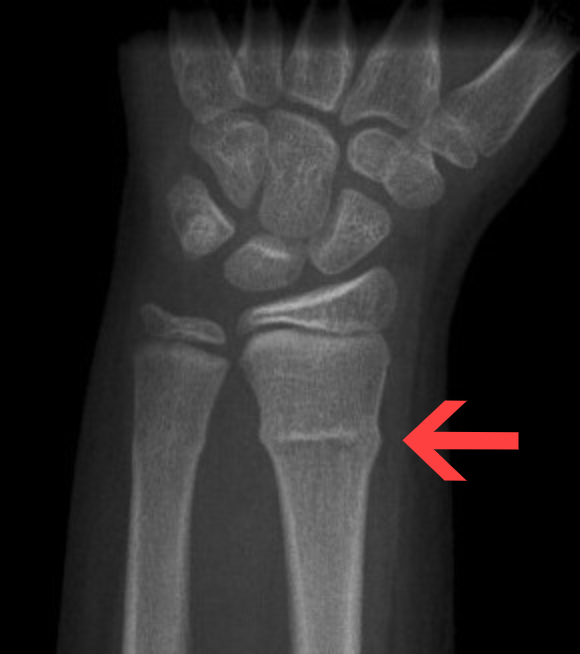

2. Salter-Harris 분류 (성장판 손상)

• Type I (Slipped): 성장판 분리 (예후 최상)

• Type II (Above): 성장판 + 골간단 (Metaphysis)

• 가장 흔함

• 예후 양호

• Type III (Lower): 성장판 + 골단 (Epiphysis)

• 관절 내 골절 (해부학적 정복 필요)

• Type IV (Through): 골간단 + 성장판 + 골단

• 관절 내 골절 (예후 불량)

• Type V (Rammed): 성장판 압박 (Crush)

• 예후 최악 (성장 정지 위험)